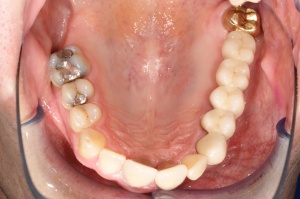

Mit der Transplantation eines freien Schleimhauttransplantats im Januar 2001 konnte die aktive parodontologische Therapie abgeschlossen werden, der Patient wurde zur Unterstützenden Parodontitistherapie in das Recallsystem der FU VIIa aufgenommen. Der Patient stellte sich dabei halbjährlich zur Durchführung von professionellen Zahnreinigungen vor, die durch die bereits beschriebenen Elemente der Erhaltungstherapie ergänzt wurden. Ein wichtiges Element der Erhaltungstherapie ist die regelmäßige parodontale Diagnostik mit der Erstellung eines Parodontalstatus, um gegebenenfalls Rezidive frühzeitig erkennen und behandeln zu können. Im Jahre 2006 kam es an einzelnen Zähnen zu Rezidiven, es konnten Sondiertiefen von bis zu 7mm sondiert werden. Es wurde daher ein Scaling/Rootplaning der rezidivierenden Taschen durchgeführt, an einzelnen Zähnen erfolgten im Jahre 2008 zudem weiterführende parodontalchirurgische Maßnahmen im Sinne von Lappenoperationen (s. Abb. 16). Im Rahmen der unterstützenden Parodontitistherapie erfolgte neben den schon erwähnten halbjährlichen professionellen Zahnreinigungen im November 2012 eine erneute subgingivale Instrumentierung an 21, 24, 28, 41, 46. Die letzte Vorstellung des Patienten erfolgte im April 2015 (s. Abb. 17, 18, 19). Dabei stellte sich die marginale Gingiva entzündungsfrei dar, die approximalen Sondiertiefen betrugen durchschnittlich zwei bis drei Millimeter, geringgradig erhöhte Sondiertiefen verbleiben an 21, 28, 36, 47. Die häusliche Mundhygiene des Patienten stellte sich wie schon über den gesamten Beobachtungszeitraum mit einem API von 30 % als gut dar. Die periimplantären Gewebe zeigten sich bei der Vorstellung im April 2015 unauffällig.